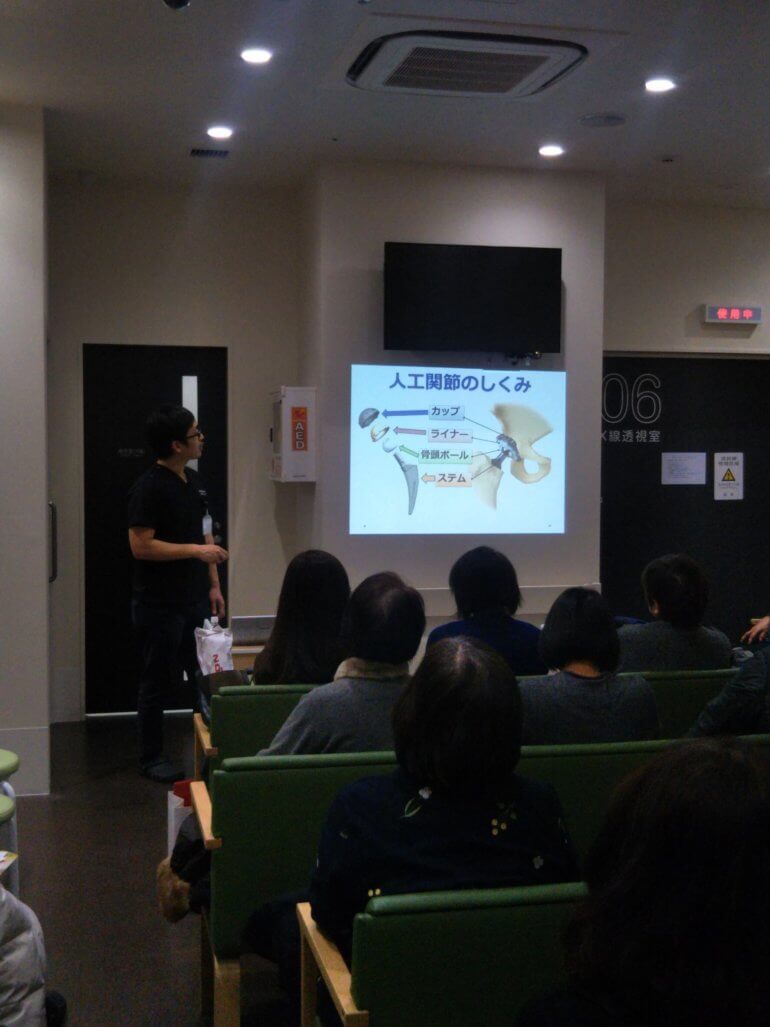

私からは

・股関節・膝関節の構造

・股関節・膝関節の痛みを引き起こす病気や原因

・保存療法と手術療法などの治療方法

・超最新の筋肉をすべて温存し、関節包の一部しか切らない人工股関節置換術

・変形性膝関節症に対する再生医療(PRP注射)

などについて説明させていただきました。

副院長の放射線科の池田先生からは

当院にあるCT、MRI、X線TVシステムの機能にくわえて

エコーガイド下筋膜リリース注射について

説明していただきました。